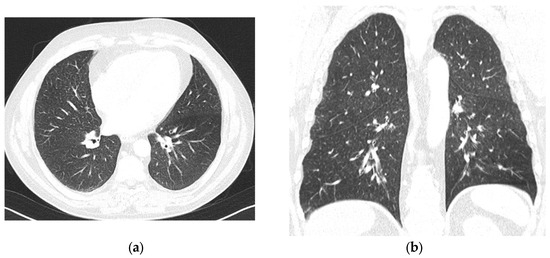

A first-line treatment with AZA as a bridge for allo-HSCT was started, with a subcutaneous dose of 100 mg/m2 for 5 days in 28-day cycles, preceded by granisetron as an anti-emetic. After the 3rd day of the first cycle, the patient developed a cutaneous erythematous, pruritic, non-urticarial rash on the thorax, abdomen, and lower limbs, without mucosal involvement. Dexchlorpheniramine was administered, improving the symptoms, and a fourth dose of AZA was administered. Granisetron was substituted by metoclopramide to eliminate additional drugs with known allergenic potential. On the 5th day, the cutaneous rash worsened, including facial involvement, and AZA was administered after premedication with hydrocortisone and dexchlorpheniramine. No other symptoms, including respiratory, vascular, or gastrointestinal ones, were observed, nor was fever. On the 13th day, the patient complained of left-sided thoracic pain, cough, and wheezing. A thoracic X-ray did not show signs of respiratory infection, and the C-Reactive Protein levels were only mildly increased at 1.27 mg/dL (reference range <0.5 mg/dL). Azithromycin was given for five days, and 10 mg prednisone was continued until the next cycle. The second cycle was started with antihistamines and prednisone 20 mg as premedication. On the 1st day of the second cycle, cutaneous symptoms reappeared, with an erythematous rash on the trunk and back and facial edema (Figure 1). Symptoms improved with additional corticosteroids and antihistaminics. Blood tests excluded infection, and eosinophil counts were normal.

Figure 1. (a,b) Cutaneous erythematous, pruriginous, non-urticariform rash located on the face, thorax, abdomen, and inferior limbs.